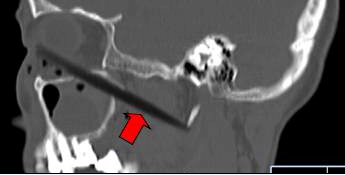

CT顯示筷子還插在腦部

取出的斷筷有9厘米

上周三,62歲的依姆林瓊(化名)在南平家中,有人在揮舞筷子時(shí),將筷子從她右眼眶插入,鼻孔瞬間出血。家人心急,用老虎鉗將筷子外端夾斷,剩下半截筷子嵌在頭面部,之后將其緊急送到福建醫(yī)科大學(xué)附一醫(yī)院。經(jīng)過(guò)1個(gè)多小時(shí)的緊急手術(shù),9厘米長(zhǎng)的斷筷被取出,由于筷子未插中眼球,患者眼睛未受影響。附一醫(yī)院耳鼻喉科副主任醫(yī)師張暉萍提醒,千萬(wàn)不可自行強(qiáng)拔已插入體內(nèi)的物體。傷者被送到附一醫(yī)院時(shí),醫(yī)生幾乎都看不到筷子了。在醫(yī)生的詢問(wèn)下,家屬這才說(shuō),當(dāng)時(shí),他們一心急,用老虎鉗將筷子外端夾斷。這下棘手了。若筷子是完整的還容易拔出,這下完全埋在眼眶下,可怎么取出?影像學(xué)檢查顯示,筷子就靠近視神經(jīng)管、頜內(nèi)血管分支,末端位于頸部大動(dòng)脈的前方。手術(shù)稍有不慎,就可能大出血。為了取出斷筷,附一醫(yī)院耳鼻喉科、頜面外科、眼科、影像科馬上聯(lián)合會(huì)診,擬定了三套手術(shù)方案。第一方案,從插入口直接拔;第二方案,從鼻腔?。坏谌桨?,鋸開(kāi)眼眶取斷筷。最終,大家選擇了第一方案,因?yàn)閯?chuàng)傷最小,由耳鼻咽喉科張暉萍副主任醫(yī)師和眼科朱學(xué)軍主任醫(yī)師聯(lián)合急診手術(shù)。醫(yī)生們先從眼眶內(nèi)切開(kāi)傷口1厘米,才看到筷子斷端,順著原先插入口,在鼻窺鏡的幫助下,邊夾邊推,將筷子順利取出。取出的竹筷長(zhǎng)達(dá)9cm,周圍有大量膿液。經(jīng)過(guò)多日抗感染治療,前日,老人才出院。